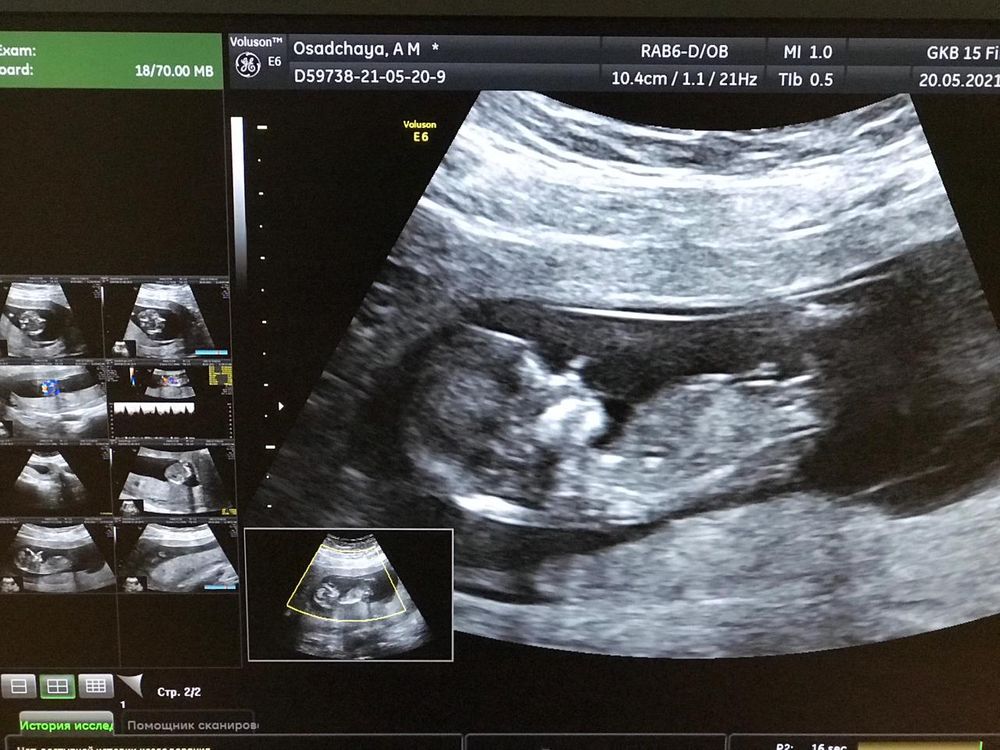

Первый скрининг и небольшая отслойка.

третья беременностьБыла сегодня на первом скрининге. Ой, как всегда, ничего не рассказала, мельком показала...

10,4 сантиметров уже, сердечко бьется 150 ударов. Пол малыш не показал.

Узистка сказала про "небольшую отслойку" а что с ней делать не сказала. Результаты будут у врача через неделю. Врач мне назначала на 3 июня визит. Вот как мне поступить? Ждать спокойно 3, ограничить секс? Пойти через неделю, когда готовы будут результаты? Бежать сейчас? но я даже не знаю сколько там сантиметров, у меня ничего на руках нет.